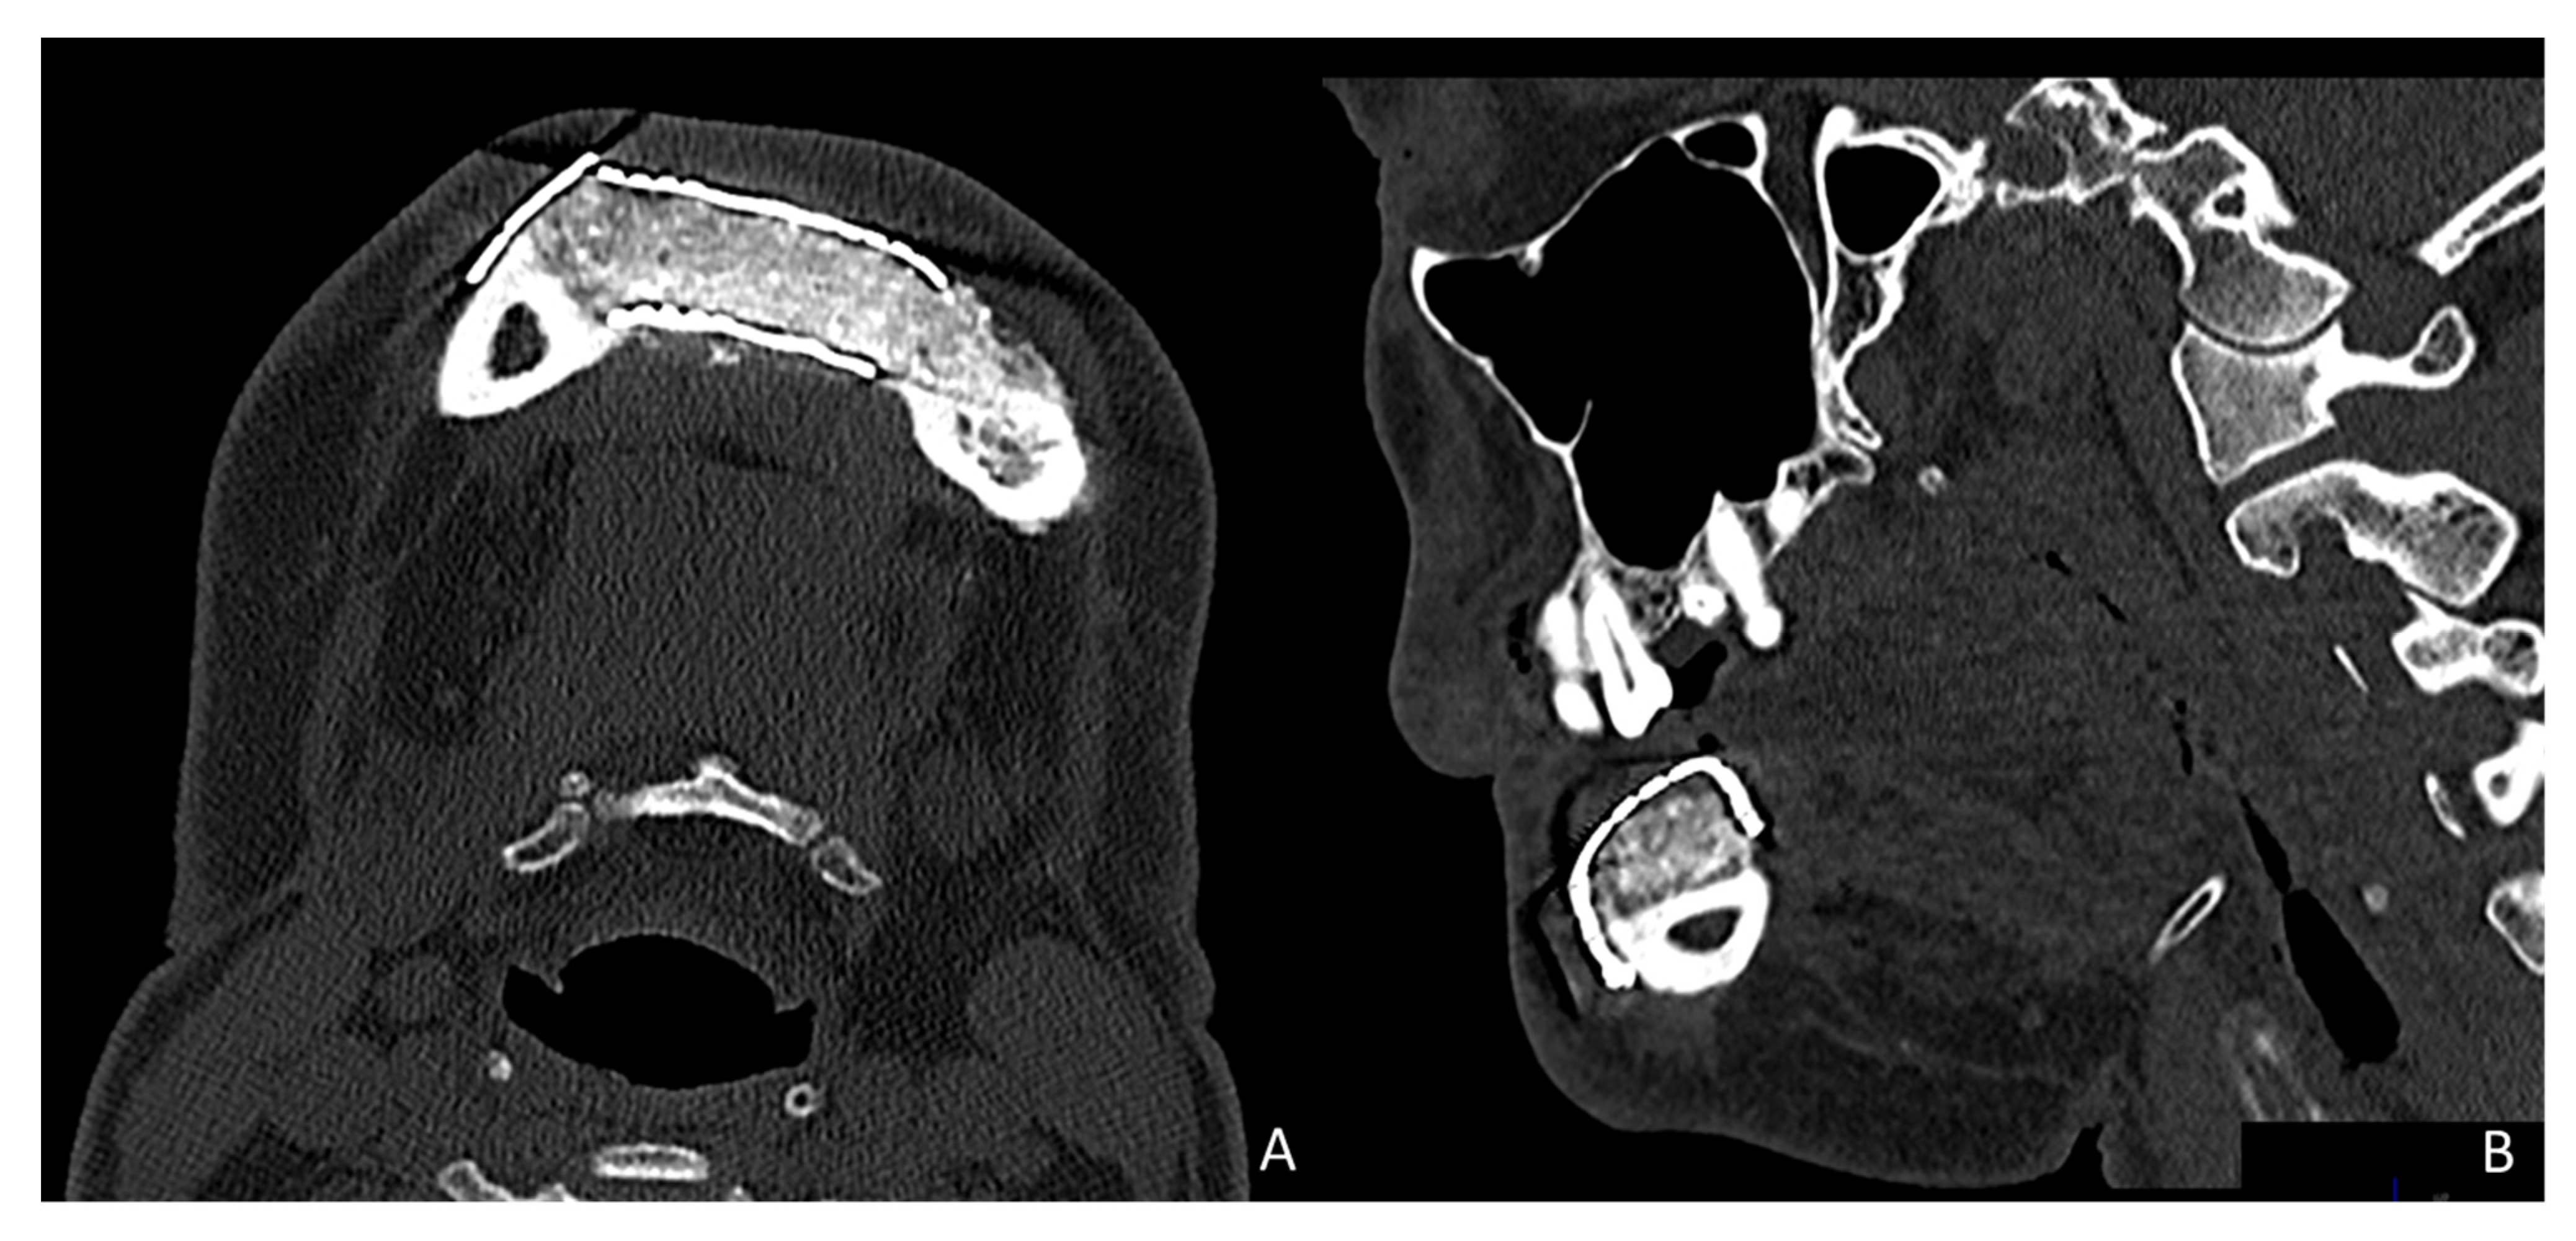

Simultaneously, a cortico-cancellous graft of the left anterosuperior iliac crest was obtained. The graft was fixed to the fibula using the CAD/CAM titanium mesh and 1.5 mm screws (Figure 5B). There was no intraoral exposure of the graft and an increase in the vertical dimension of the fibula was achieved and demonstrated by panoramic radiograph and CT scan (Figure 6A,B and Figure 7A,B).

CT Scan and CBCT were performed in the postoperative follow-up, and bone volume and bone resorption (Figure 13 and Figure 14) were evaluated by the Radiology Department of the hospital. A morphing reconstruction was performed to compare the lower facial third showing an improvement in the aesthetic profile and facial projection (Figure 15).

Figure 7. Postoperative CT scan. (A) Axial CT Scan demonstrating the stability of the transverse dimension of the fibula with respect to the remnant mandible. (B) The three-dimensional preservation of the iliac crest graft with CAD/CAM mesh makes it possible to double the height of the fibula.

Figure 13. CT Scan and CBCT were performed in the postoperative follow-up, providing relevant quantitative data regarding bone volume and bone resorption.